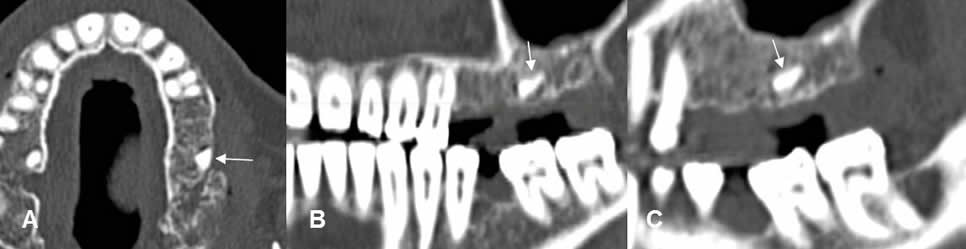

Fig 20 A. Raíz retenida.

A: TAC axial, B: TAC reconstrucción panorámica y C: TAC sagital.

Ausencia de piezas, en el lado izquierdo del maxilar, con fragmento de raíz retenida.